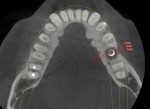

Numerous publications have covered the use of anorganic bovine bone mineral (ABBM), such as Bio-Oss® (Geistlich Pharma North America, geistlich-na.com), for ridge augmentation. Compared to autogenous block grafts, there is no chance of morbidity in the donor site. Also, more bone formation was noted when ABBM was combined with a high percentage of autogenous bone from the anterior mandible and placed under a titanium mesh for an anterior maxillary ridge augmentation.5 However, closely examined histologic specimens showed no osteoclastic activity and no resorption of the xenograft particles. Also, four of the seven meshes became exposed during healing.5 Any graft that is not resorbed and not either replaced by bone or surrounded by vital bone may potentially interfere with osseointegration. An example of this is shown in Figure 1 and Figure 2 in a patient after immediate-socket implant placement with an unknown graft by another surgeon. The periapical x-ray (Figure 1) shows crestal bone loss on the distal aspect with questionable bone formation on the mesial of the implant adjacent to the graft. On CBCT evaluation (Figure 2), a trough around the shoulder of the implant is evident.